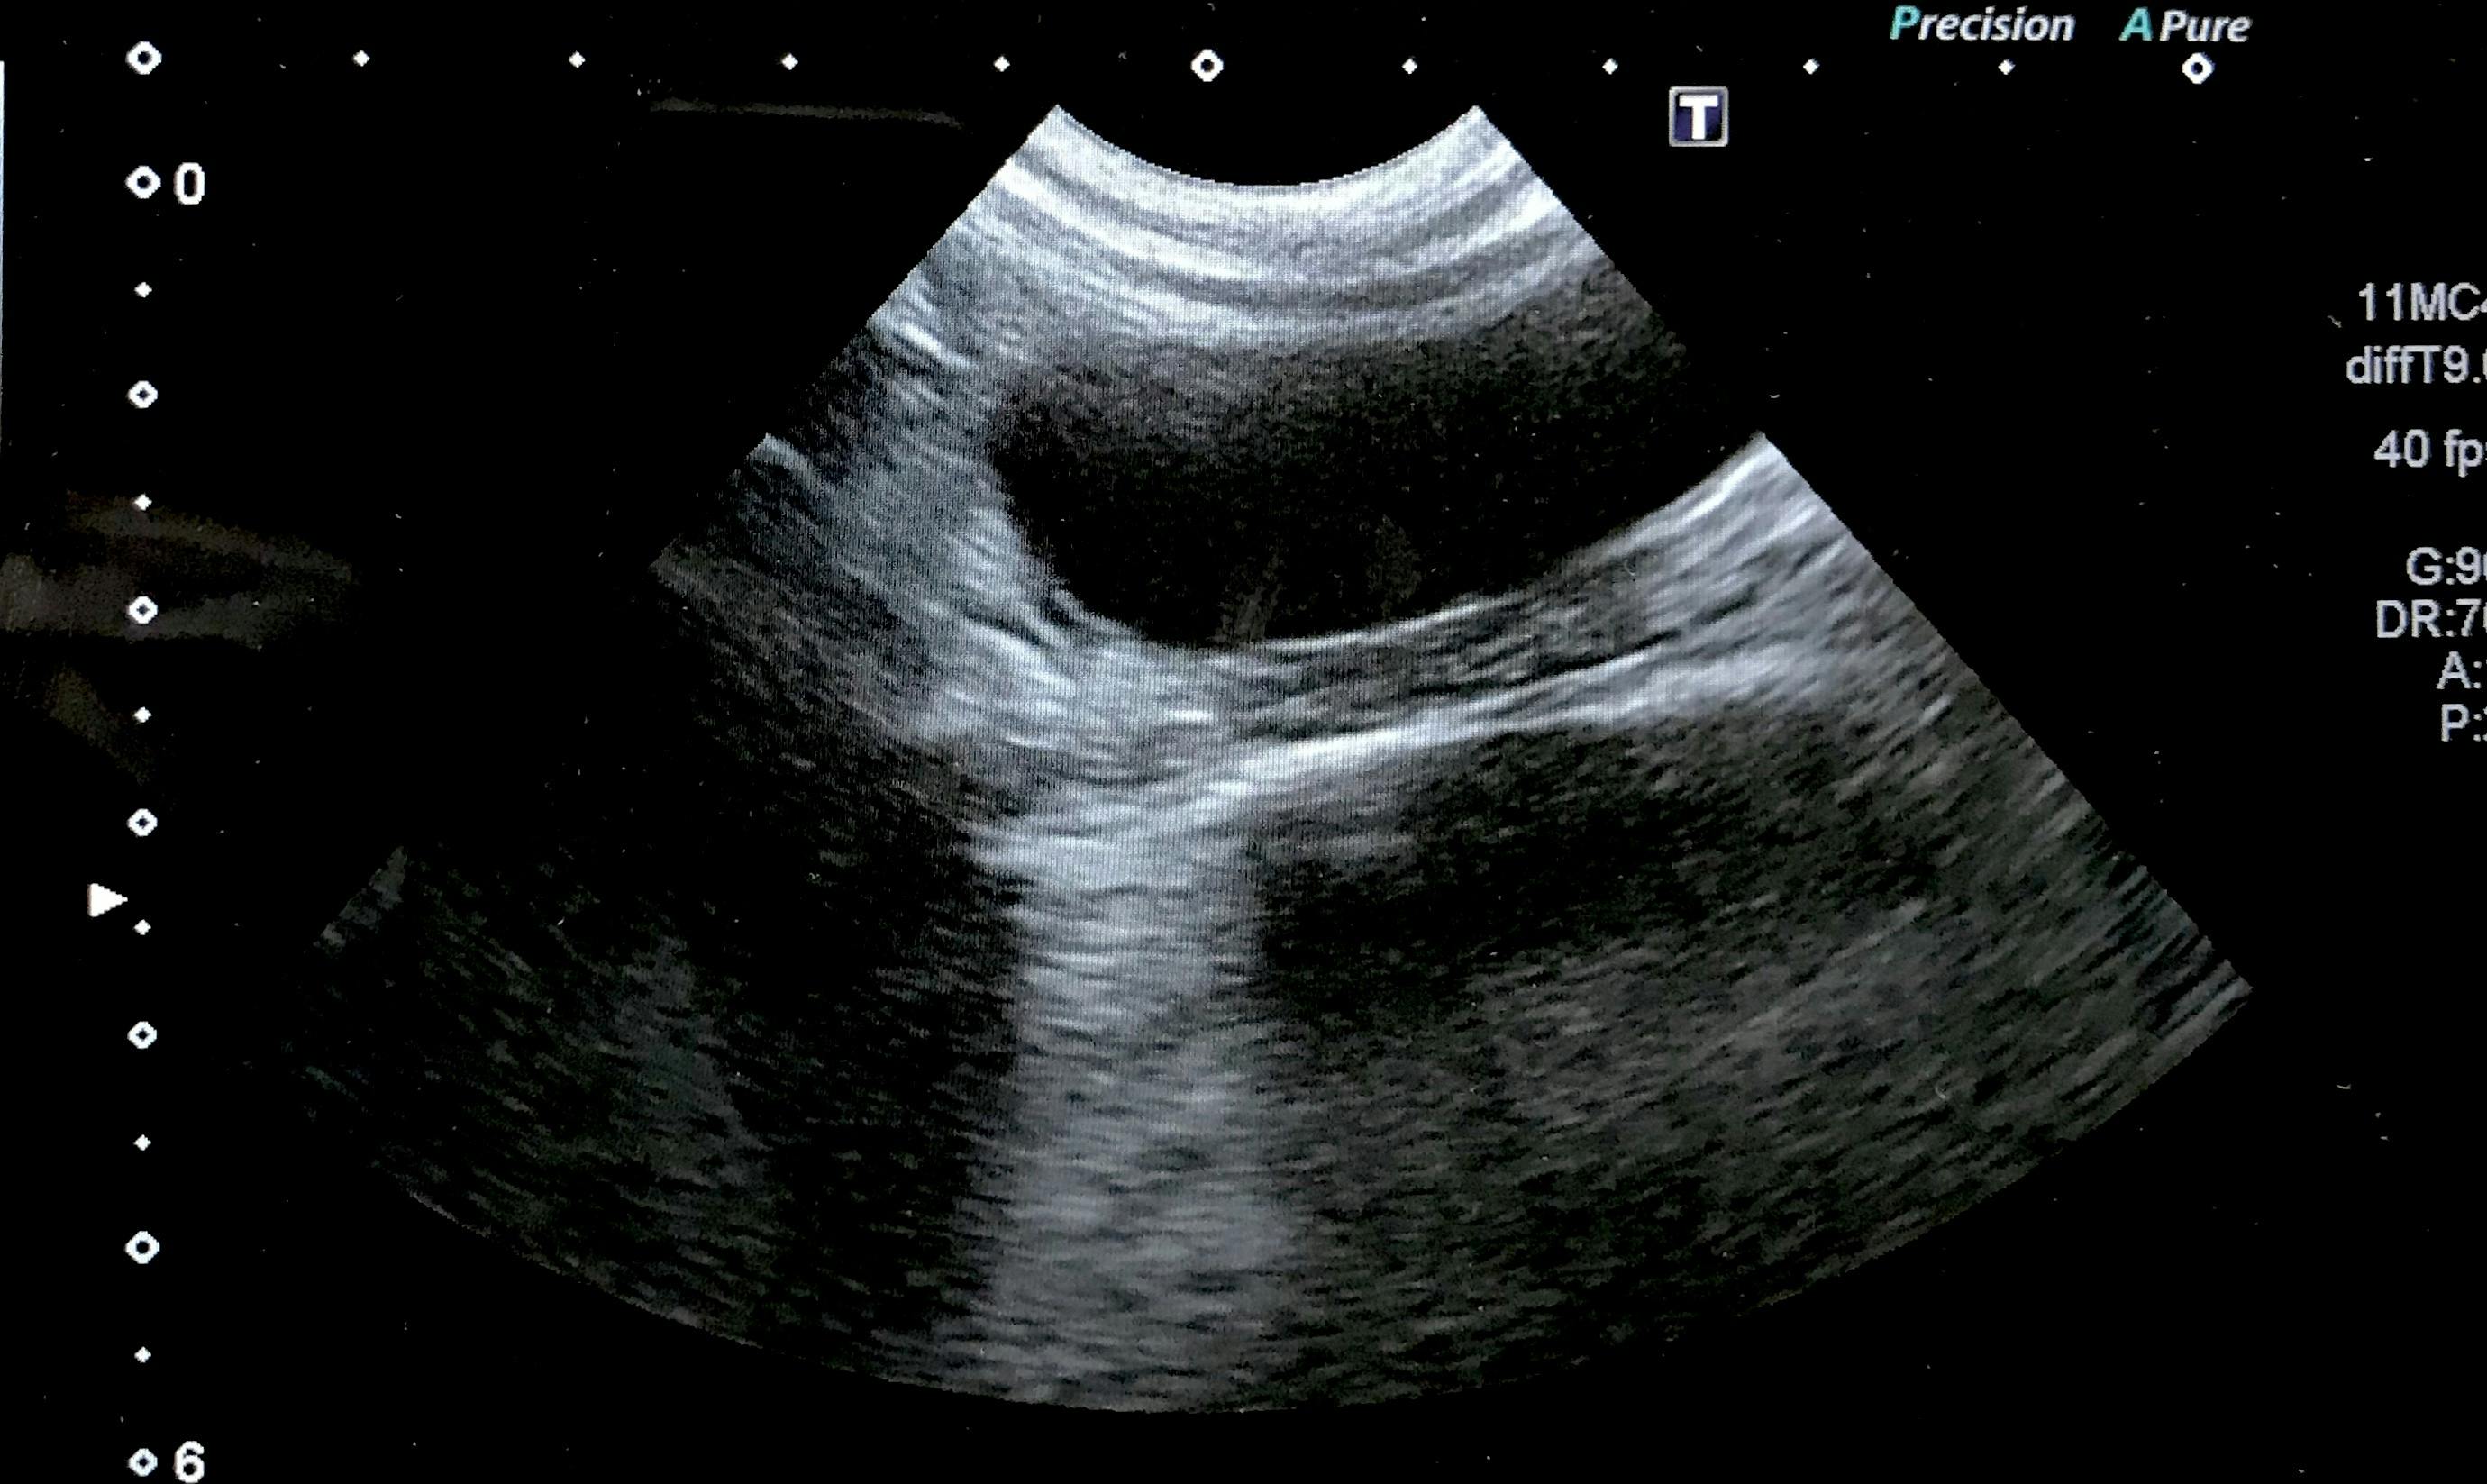

お腹に肉芽腫のようなものがあるとエコー写真を見せられ3センチほどの塊が写っていました。

検査で血液検査、エコーを見ながら説明してくださり「FIP確定です」と宣言されました。腹水が溜まっているのと肉芽腫があることからウェットドライ混合タイプでした。

↑肉芽腫

↑腹水